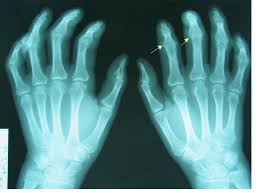

Calcium pyrophosphate deposition disease (CPPD) occurs when calcium pyrophosphate (CPP) crystals form near cartilage cells, sometimes leading to joint inflammation, pain, and swelling. It is often called pseudogout because of its clinical similarity to gout, yet much less is known about CPPD than about gout and other forms of inflammatory arthritis.

Rheumatologist Sara Tedeschi, MD, MPH, her colleagues at Brigham and Women’s Hospital in Boston, and fellow at the Medical College of Wisconsin, wanted to expand the knowledge base by investigating whether patients with CPPD disease are at increased risk for fractures. Previous studies had shown a link between low bone density and CPPD. Recent data from experimental models suggest that increased formation of osteoclast (cells that break down old bone) due to loss of function of osteoprotegerin (a protein that normally inhibits bone resorption) may contribute to the pathogenesis of the disease.